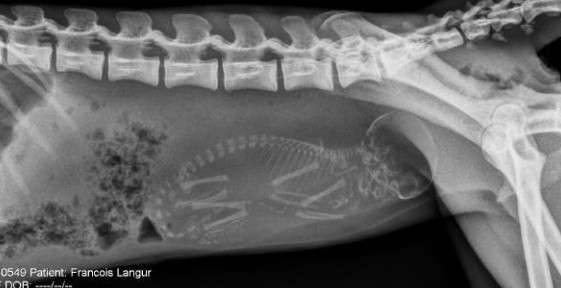

▼怀孕的猫咪